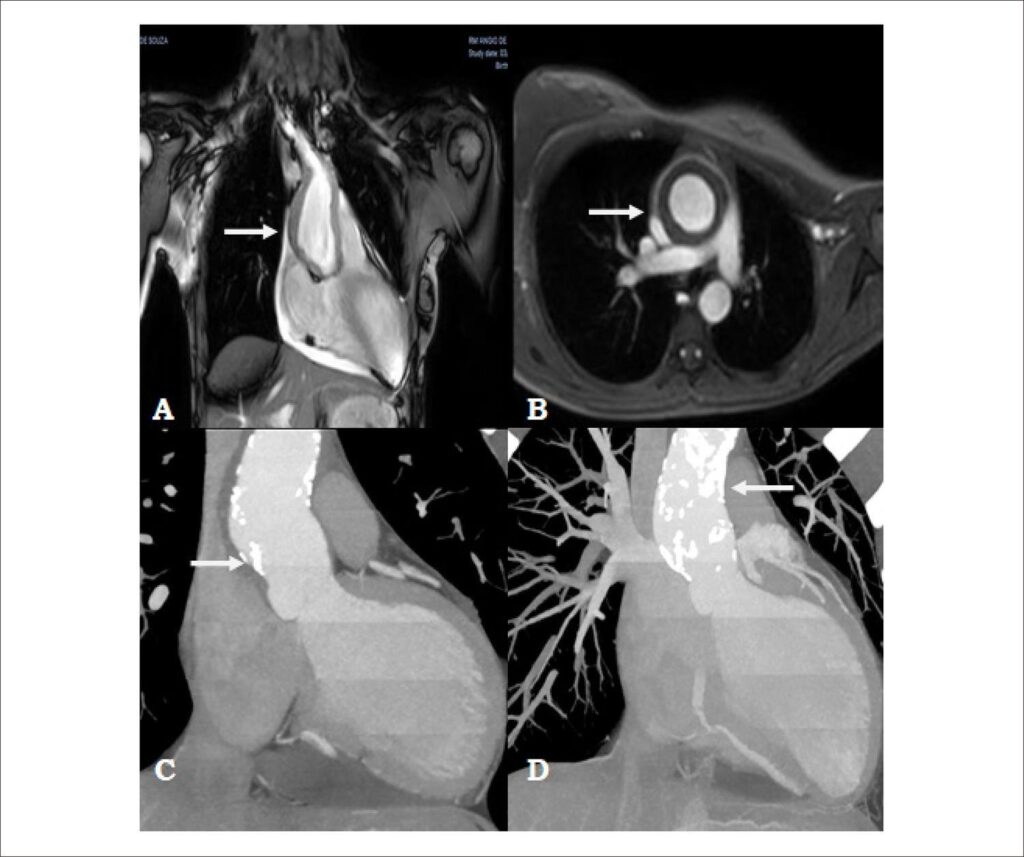

A Arterite de Takayasu (AT) constitui doença de múltipla apresentação, podendo acometer diversos sistemas. Acomete principalmente mulheres nas primeiras décadas de vida. Reportamos um caso de paciente com 19 anos de idade com AT, com diagnóstico de aneurisma de aorta ascendente e doença arterial coronariana grave em artéria coronária direita (ACD) e tronco de coronária esquerda (TCE), sendo submetida a implante de enxerto de Dacron supracoronariano em aorta ascendente e revascularização miocárdica com dupla artéria torácica interna. Evoluiu de forma satisfatória no pós-operatório, seguindo em acompanhamento clínico em nosso serviço.